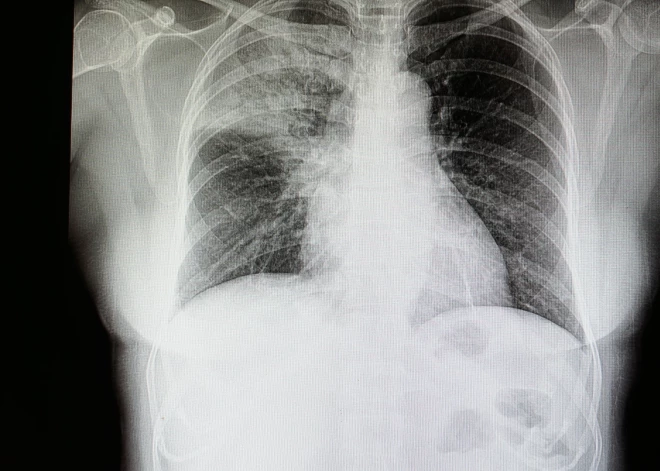

Pneimonijas uzliesmojumu, kas izraisīja četru cilvēku nāvi Argentīnas ziemeļrietumos, izraisīja Legionellas baktērijas, paziņojušas valsts veselības aizsardzības iestādes.

Uzliesmojums, kurā tika reģistrēti 11 saslimšanas gadījumi, bija saistīts ar vienu privātu veselības aprūpes klīniku Tukumanas pilsētā, paziņoja Veselības organizācija.

Argentīnas Veselības ministrija ir informējusi, ka saslimšanas cēlonis ir legionellas, un piebilda, ka iestādes pašlaik izmeklē slimības avotu.